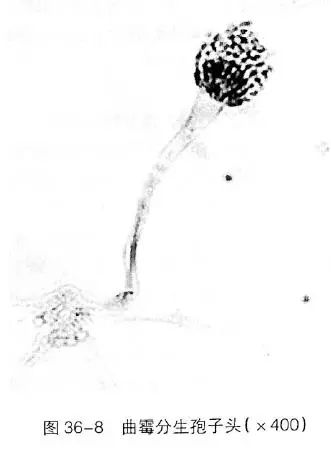

曲霉:分支状多细胞性有分隔菌丝 + 分生孢子。典型的为45°分支的有隔菌丝。

上图是曲霉的病理图片。